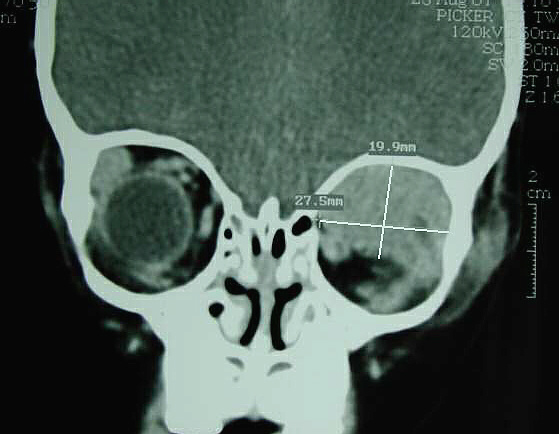

CT of head demonstrating Left orbit tumor, with proptosis and infiltration of adjacent soft tissues.